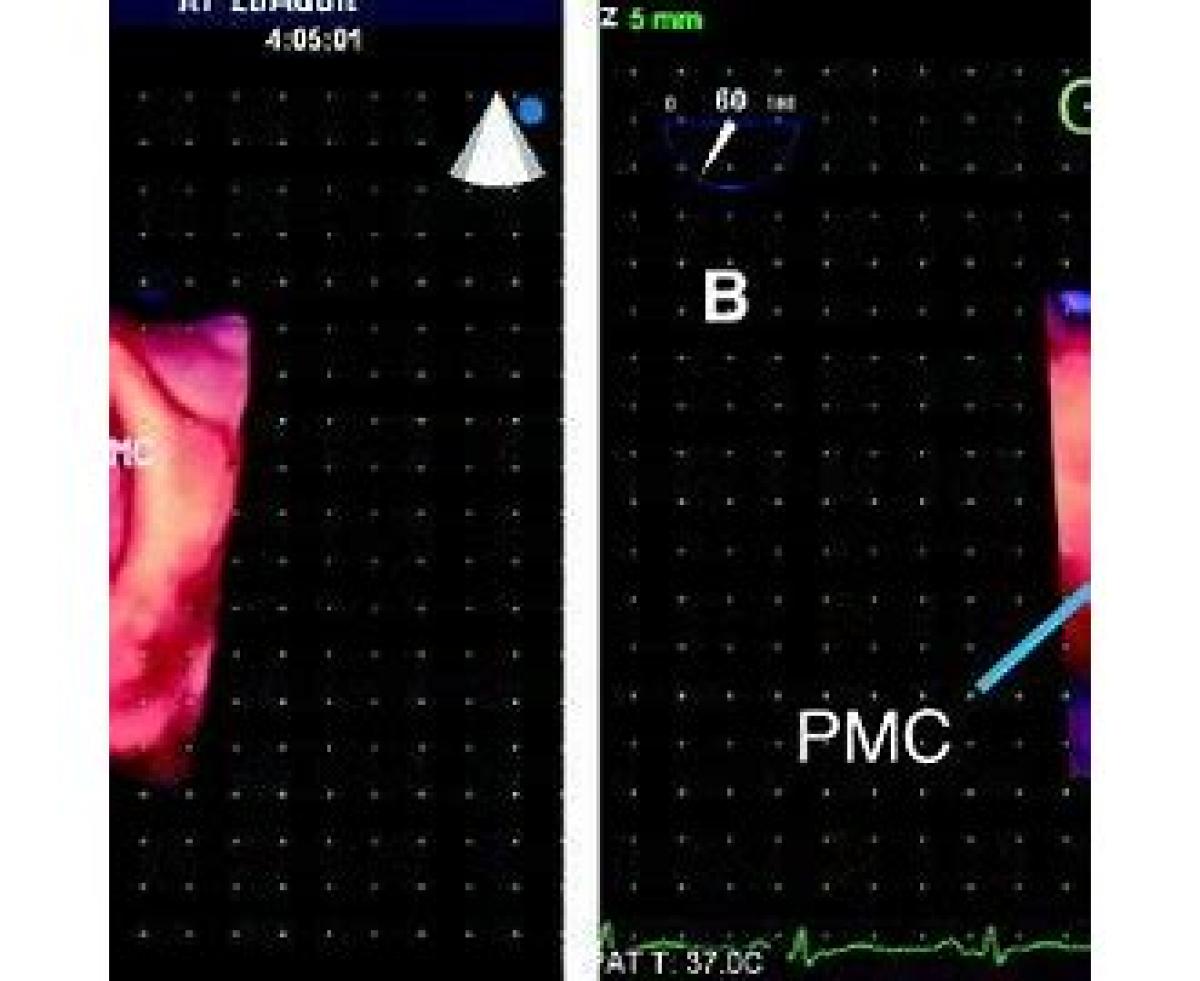

مخفف AMVL

Anterior Mitral Valve Leaflet

اکوی قلب